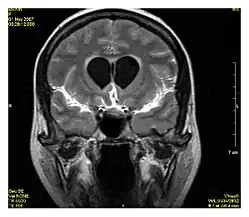

| Double inversion recovery | DIR | Simultaneous suppression of cerebrospinal fluid and white matter by two inversion times.[79] | High signal of multiple sclerosis plaques (pictured).[79] |

| |